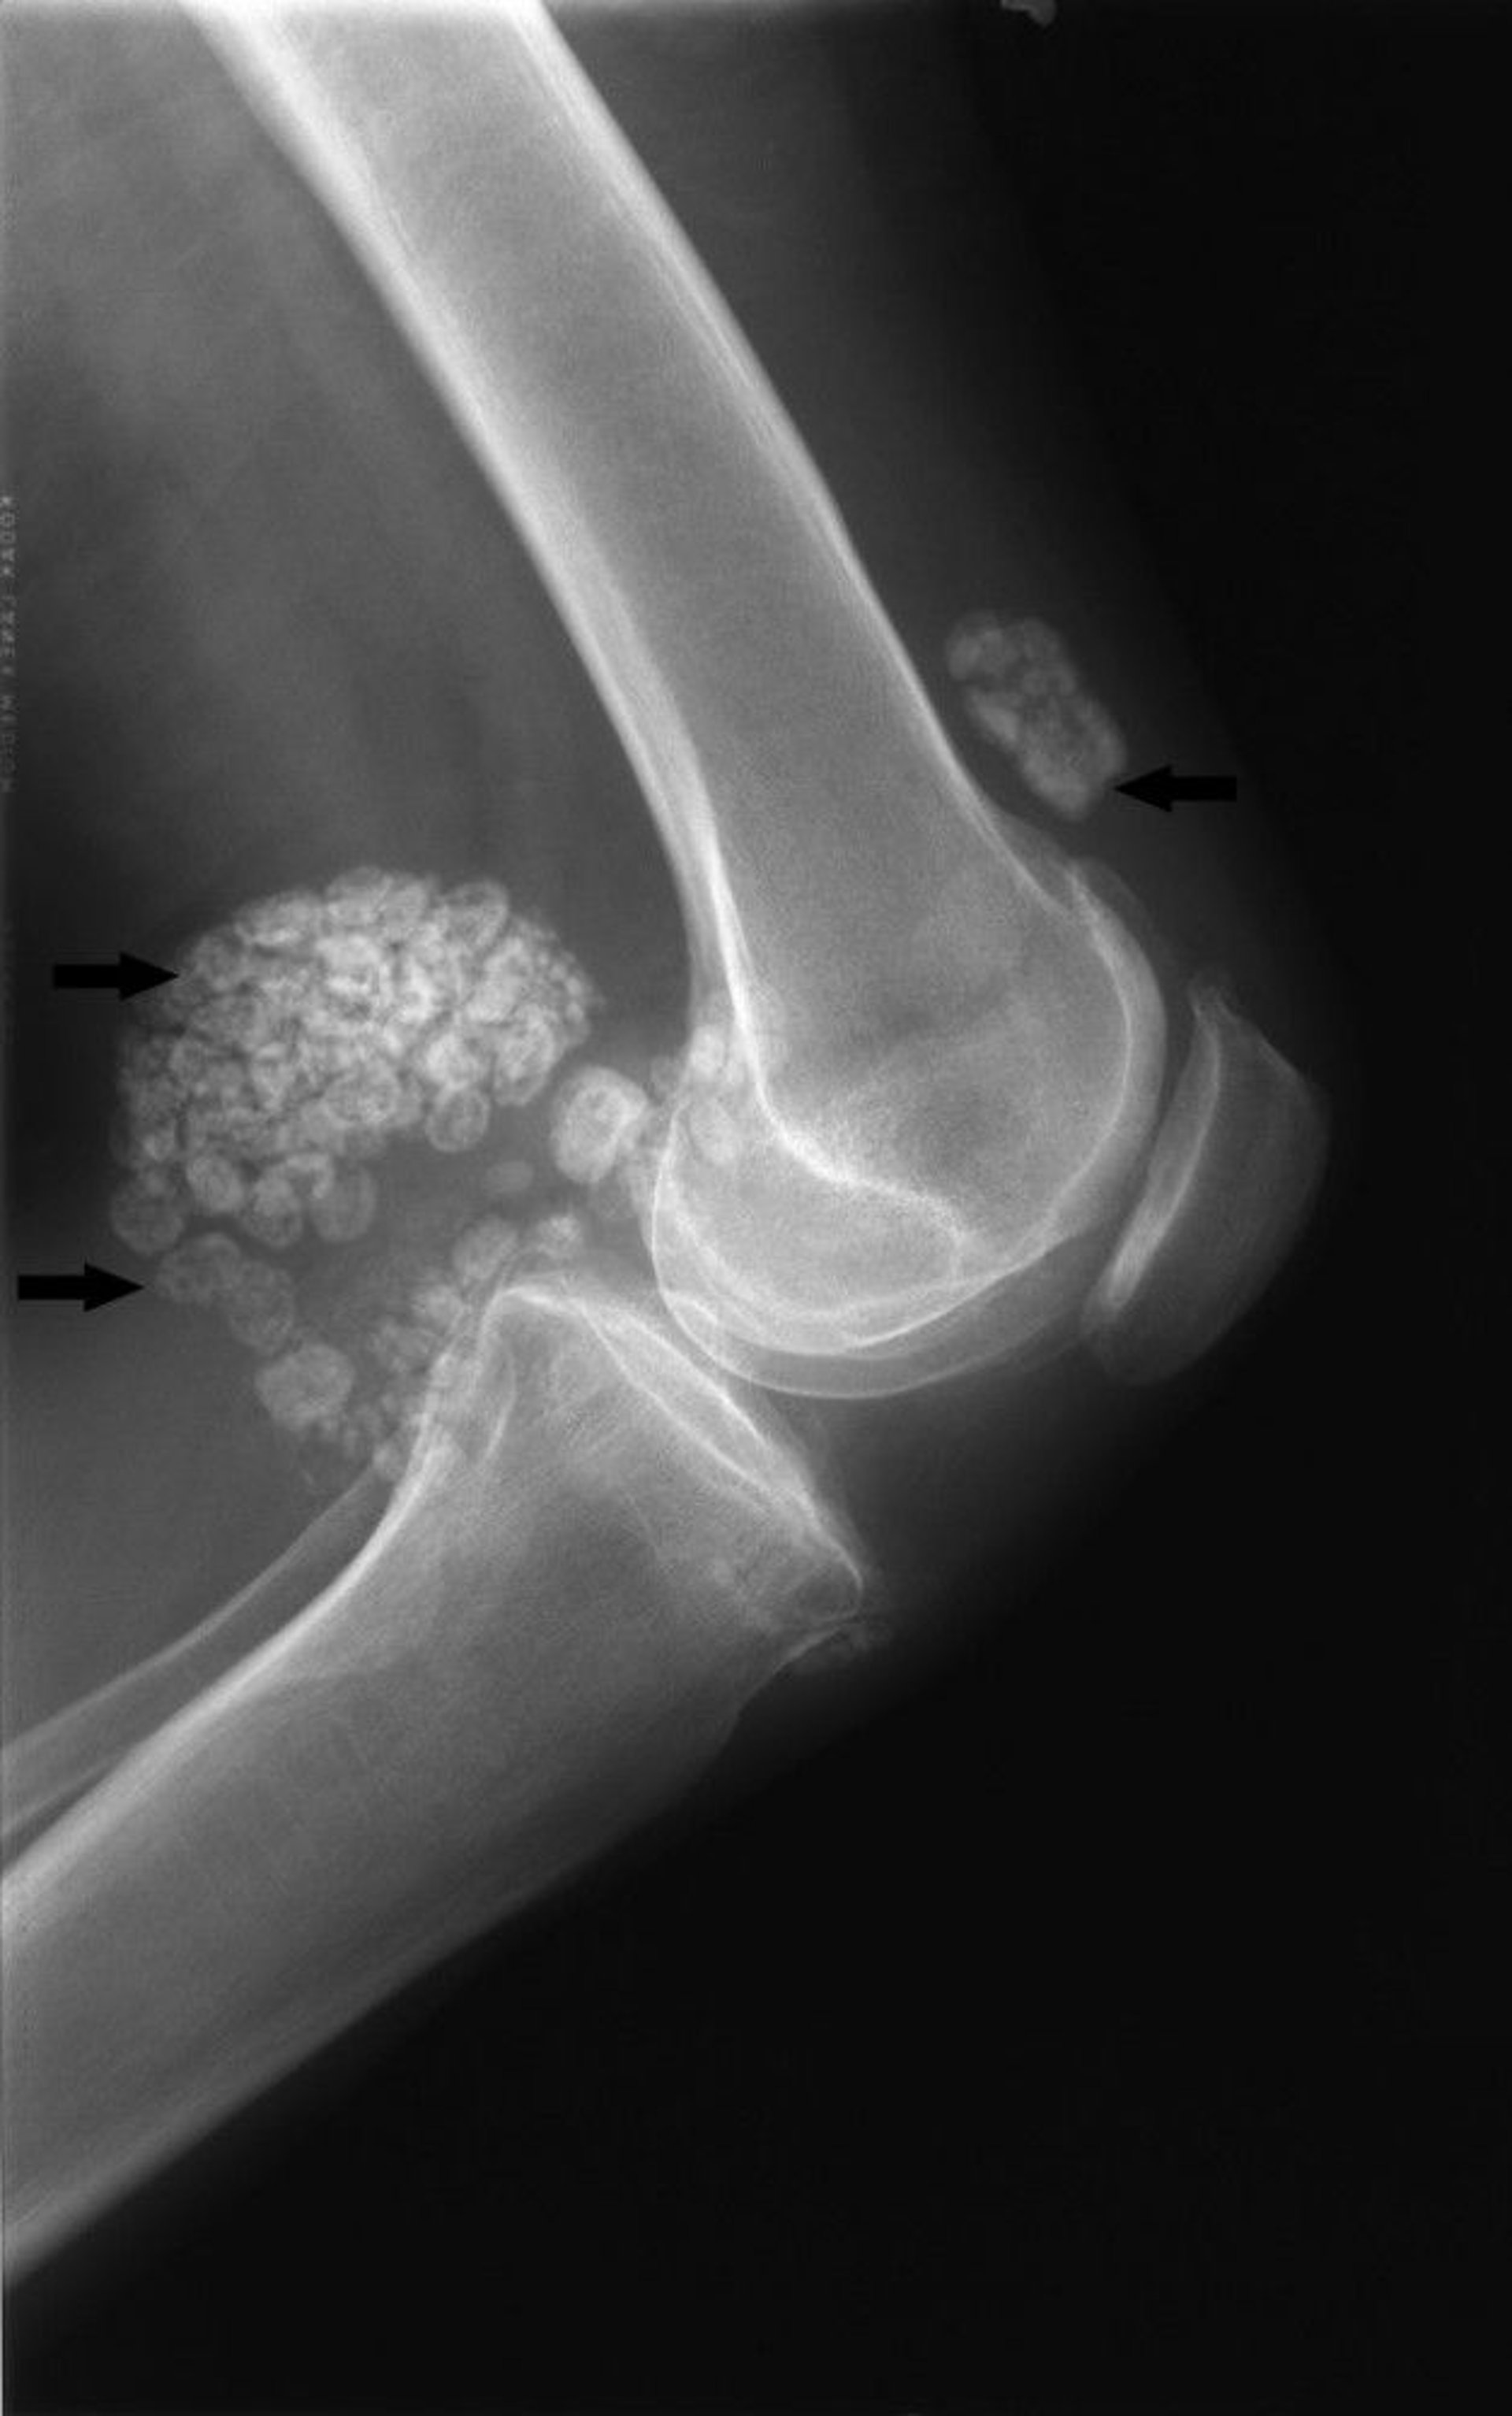

Synovial Chondromatosis

This radiograph of the knee shows multiple large calcified joint bodies both in front of and in back of the joint (arrows), which is typical of synovial chondromatosis.

Image courtesy of Michael J. Joyce, MD, and Hakan Ilaslan, MD.